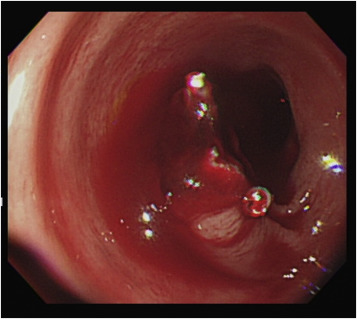

A 65-year-old man was referred to our emergency department for surgical intervention of refractory post-polypectomy hemorrhage. The patient had a medical history of hypertension, diabetes, and gout. He was not taking aspirin or other anticoagulant medication. According to the referral sheet, the polyp was 2 cm in diameter with a thick stalk in the descending colon. The referring physician had administered a prophylactic injection of diluted epinephrine into the polyp base, with two prophylactic endoclips placed before the procedure. Massive bleeding developed immediately after the procedure, and the referring physician attempted hemostasis with further injection therapy and heat-probe coagulation; however, it was not successful. The patient went into shock and was transferred to our hospital 2 h after the procedure. At the emergency department, the patient was pale and hypotensive, with a systolic blood pressure of 84 mmHg with tachycardia (heart rate: 110 beats/min). Blood test revealed a drop in hemoglobin from 14.2 g/dL to 8.9 g/dL and a normal coagulation profile. An emergent abdominal computed tomography (CT) scan revealed active contrast extravasation in the descending colon (Figure 1 , arrow), and a proctology surgeon was consulted for surgical intervention. After discussion with the patient, the patient requested a second attempt at colonoscopy to control his bleeding, and an emergent colonoscopy was performed. A large amount of fresh bloody content was found between the rectum and the descending colon. After copious irrigation with water and positional change, the bleeder source was identified (Figure 2 ).

Endoscopic finding of active bleeding from a polypectomy wound. Two endoclips ...

Figure 2.

Endoscopic finding of active bleeding from a polypectomy wound. Two endoclips remained in place.